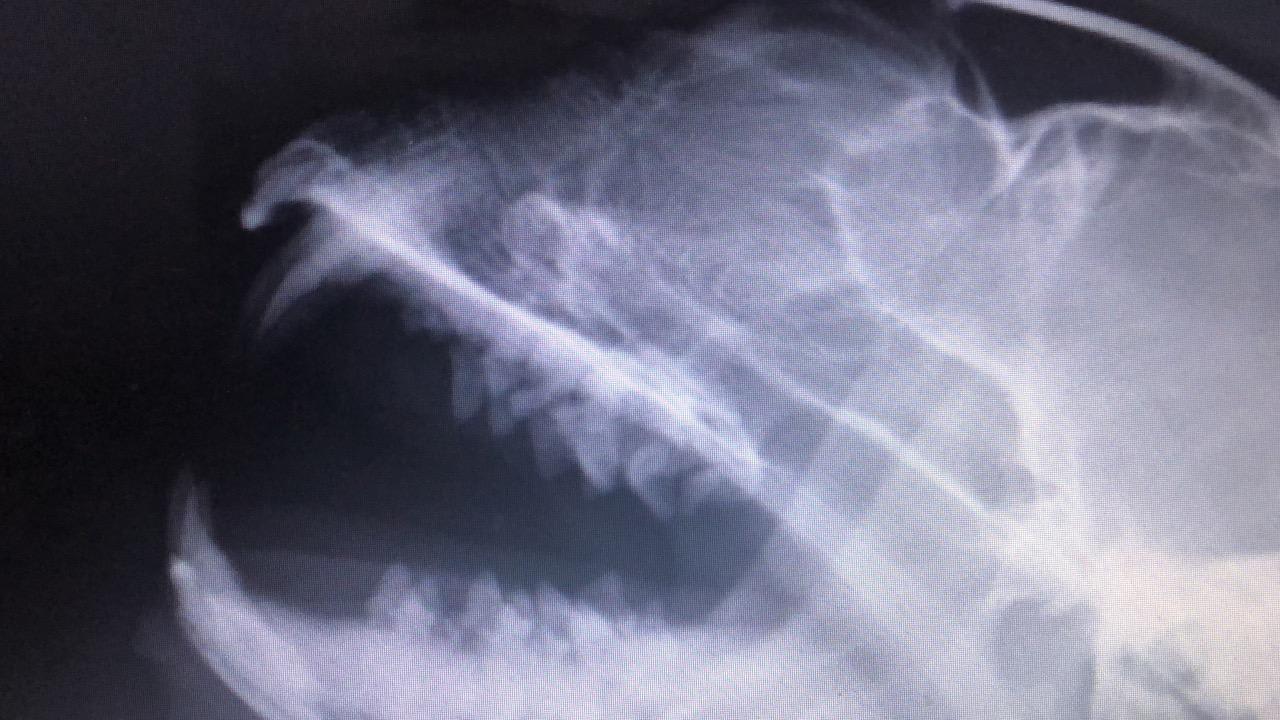

Hi. My cat have a breathing problem. In the photos you can see an object in noise. But no one couldnt undertand And ı have A video . You can hear the Voices.

This could be a polyp or a tumor or a foreign object. This will need to be removed. If your local vet cannot remove that, you may need to take your cat to a clinic in a larger city or at the veterinary hospital at the nearest veterinary university. Unfortunately without seeing the cat's nose with the foreign body, there is no way I can suggest a treatment or possible cause.